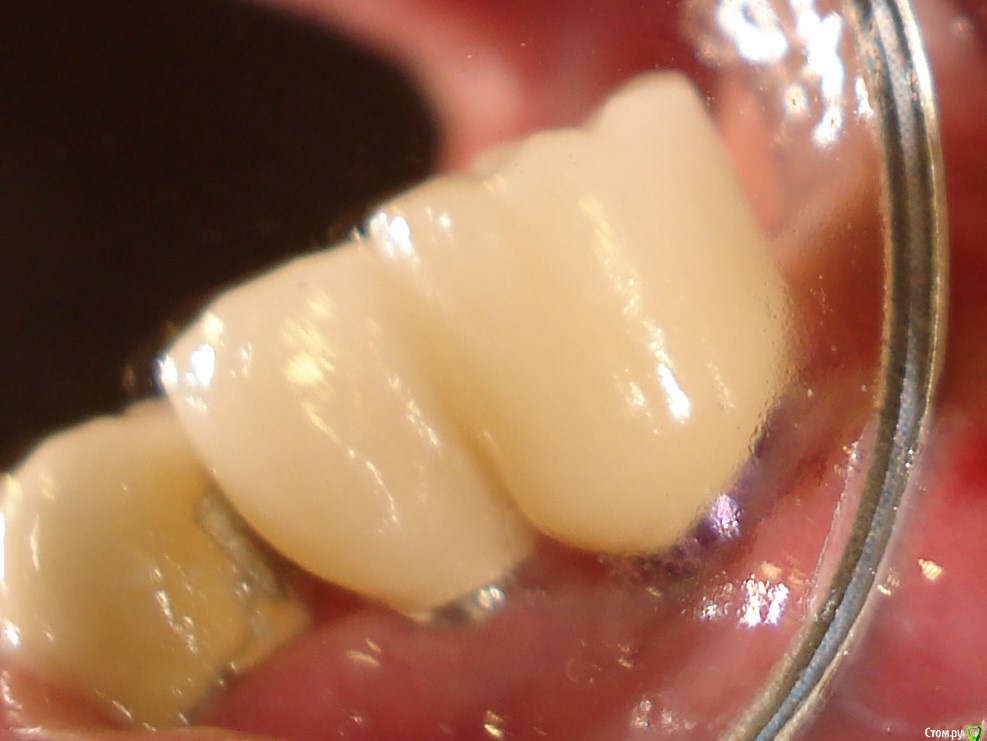

Antikwar Опубликовано 26 ноября, 2017 Поделиться Опубликовано 26 ноября, 2017 Доброго времени суток .Хотелось бы узнать компетентное мнение, врачей, З.техников. Вчера было установленно 2 моста (оксид циркония) на имплантанты перед низ и 2 коронки с боку правая сторона низ ..НА мой не опытный взгляд конструкция и сама работа не качественная и эстетика здесь полностью отсутствует. 1.Видно тело абатмента в обоих конструкциях. 2.Мост и коронки висят в воздухе и не прилегают к десне,как в первом так и во втором случае. Между десной и мостом (перед низ) проходит спичка. Вопрос, должен ли мой доктор переделать эту (на мой взгляд) не качественную работу ! Что вы мне посоветуете .... Заранее благодарю всех откликнувшихся. Ссылка на комментарий

chervoncevdaniil Опубликовано 26 ноября, 2017 Поделиться Опубликовано 26 ноября, 2017 Доброго времени суток .Хотелось бы узнать компетентное мнение, врачей, З.техников. Вчера было установленно 2 моста (оксид циркония) на имплантанты перед низ и 2 коронки с боку правая сторона низ ..НА мой не опытный взгляд конструкция и сама работа не качественная и эстетика здесь полностью отсутствует. 1.Видно тело абатмента в обоих конструкциях. 2.Мост и коронки висят в воздухе и не прилегают к десне,как в первом так и во втором случае. Между десной и мостом (перед низ) проходит спичка. Вопрос, должен ли мой доктор переделать эту (на мой взгляд) не качественную работу ! Что вы мне посоветуете .... Заранее благодарю всех откликнувшихся.СУдя по фото у вас убыль костной и мягких тканей в области ипмлантов.А состояние соседних коронок на зубах вас не смущают? Ссылка на комментарий

chervoncevdaniil Опубликовано 26 ноября, 2017 Поделиться Опубликовано 26 ноября, 2017 Конечно же смущает,.... но они в плане на лечение.НО как же ответ на мой вопрос ?Так это и есть ответ на ваш вопрос,конечно по фото судить сложно,нужен рентген,но если это убыль костной ткани,то коронки могут быть досажены корректно,относительно импланта,проблема может быть в том,что уже кость ушла ниже уровня имплантата,а это коронкой не перекрыть никак 2 Ссылка на комментарий

chervoncevdaniil Опубликовано 26 ноября, 2017 Поделиться Опубликовано 26 ноября, 2017 А, что нельзя сделать коронки по больше, что бы они легли на десну, ведь так просто????Если то,что выступает над десной уже сам имплант,а не абатмент(а скорее всего так оно и есть),то нельзя Ссылка на комментарий

krokomot Опубликовано 27 ноября, 2017 Поделиться Опубликовано 27 ноября, 2017 целевая зона на снимке замылена, четкости нет, исходя из ваших фотографий проблемма не в коронках, а в позиции имплантатов - видна шейка имплантата, так быть не должно. нужны прицельные снимки этой области. Учитывая обстоятельства коронки изготовливаются исходя из положения имплантатов.и я так понимаю вас запротезировали из позиции то что есть, и вая явно нужно что-то делать. Ссылка на комментарий